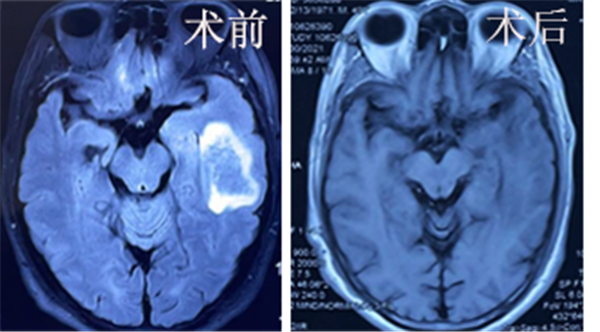

急诊CT及MRI显示该患者中耳腔巨大胆脂瘤破坏中颅窝、后颅窝骨质,并伴有4cm×7cm大小的颞叶脓肿。经过耳鼻咽喉头颈外科与神经外科多次讨论,制定了详细的诊治方案。手术当天,古茹护士长调配脑科专用器械,宋正川教授负责麻醉,王文护士协助手术,耳鼻咽喉头颈外科病院吴宝俊教授、李阳副教授、王军利主治医师先行岩骨次全切除术,完全切除颞骨胆脂瘤,并充分去除中颅窝底骨质,显露中颅窝硬脑膜。神经外科刘重霄教授团队精准定位颞叶脓肿,自中颅窝底放入脑室引流管,排出脓液后将引流管固定于耳后皮下。吴宝俊教授耳科团队继续手术,封闭咽鼓管鼓室口,关闭外耳道,取腹部脂肪填充术腔。术后患者生命体征平稳,意识清楚,头疼消失,无面瘫,眩晕,无脑脊液漏,术后5天拔除引流。术后8天复查CT及MRI,见中耳病灶清理干净,颅内脓肿明显缩小,顺利出院。